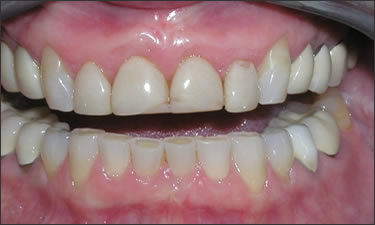

This patient experienced many areas of gum recession, primarily on the upper and lower front teeth. This patient's own tissue was used to correct the problem.